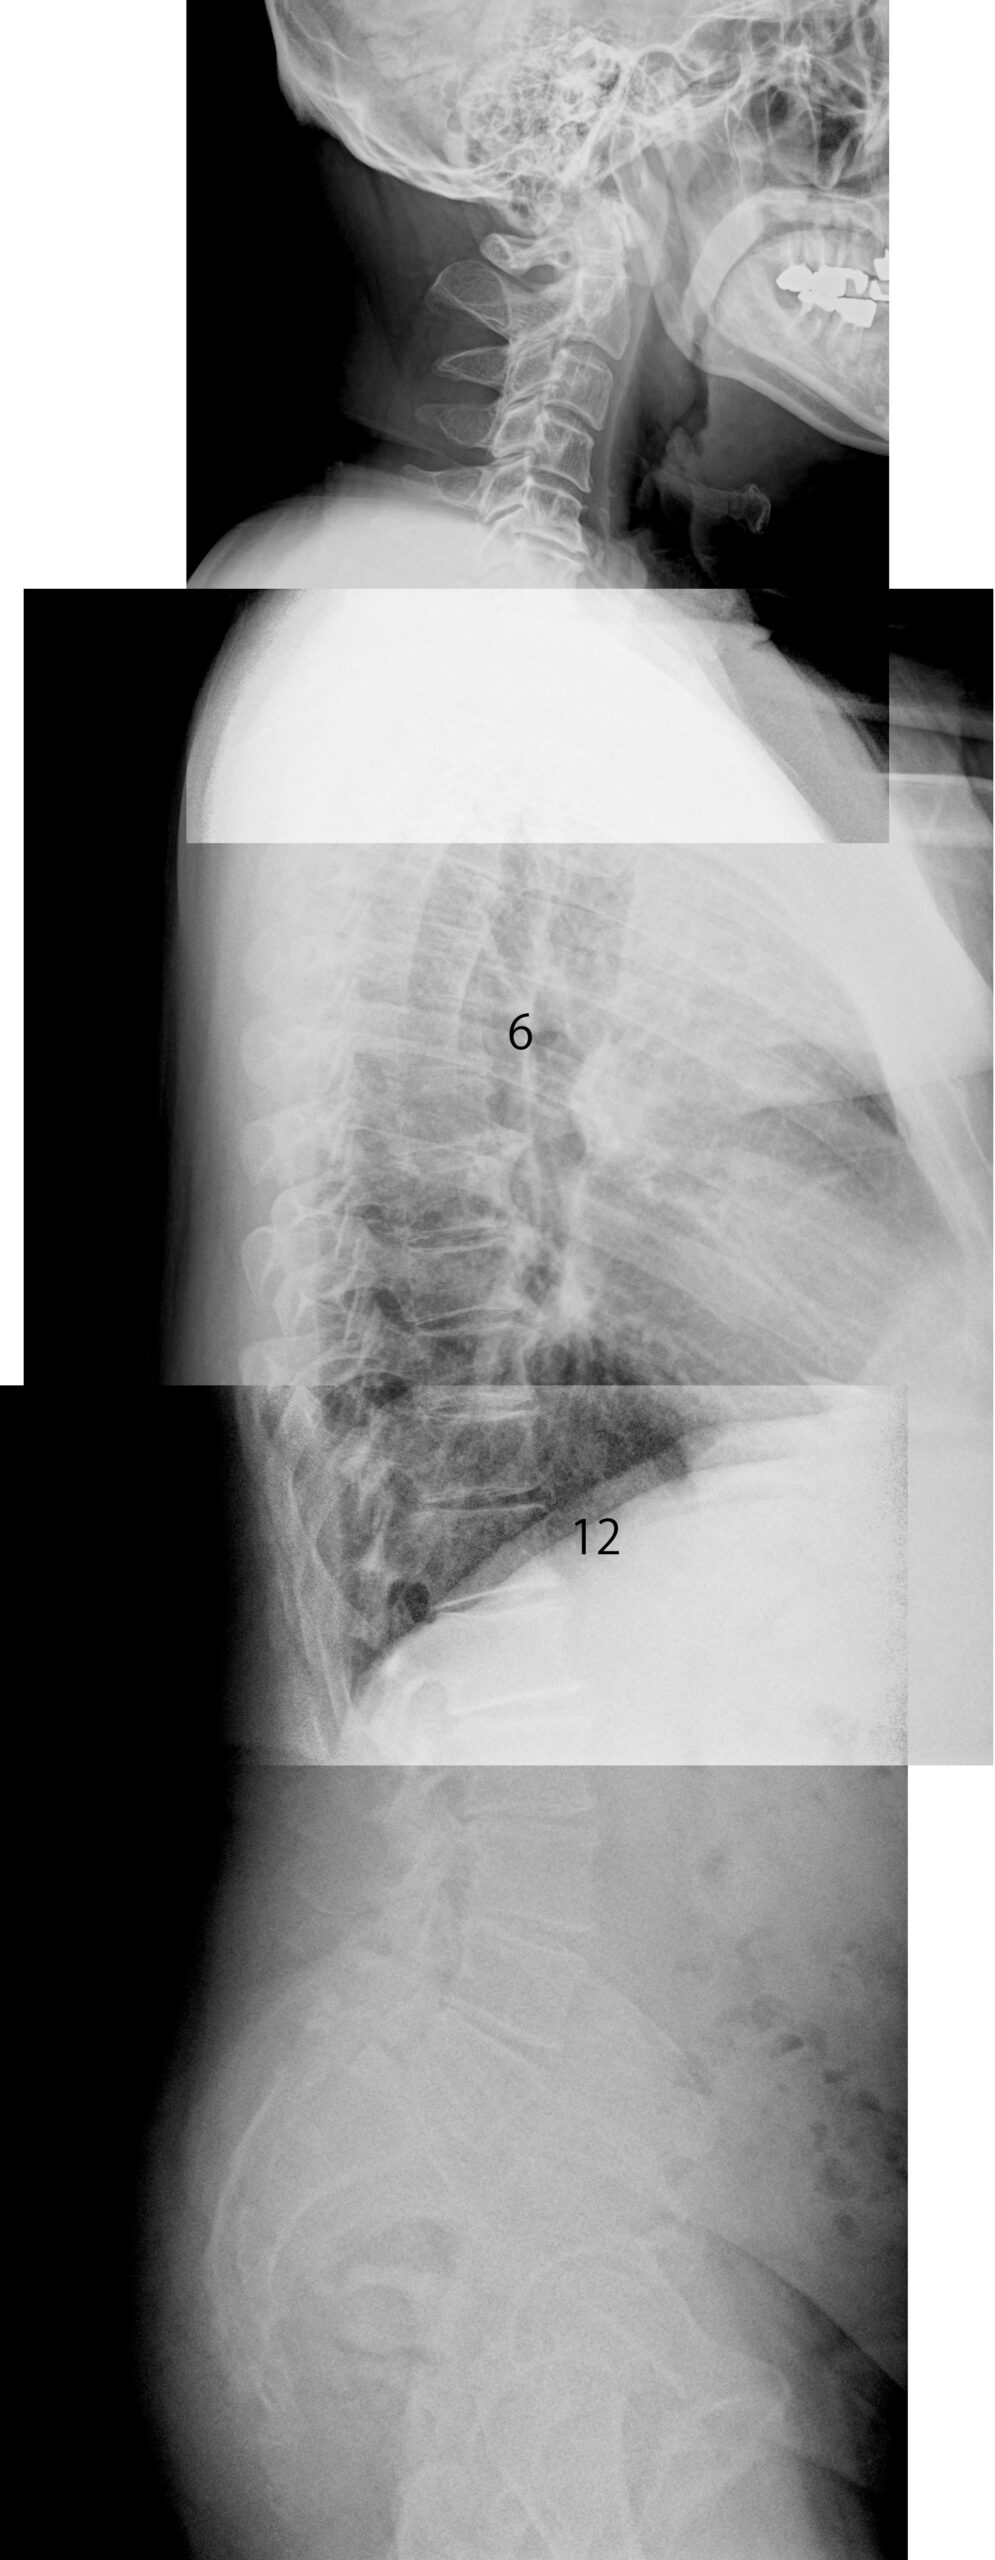

画像上ではL5すべり症およびL5/S1椎間板の高度変性が確認され、L2/3レベルにも圧迫骨折様の所見がみられた。一方で、膀胱直腸障害や両下肢の著明な筋力低下といった重篤な馬尾症状は認められていない。仰臥位で症状が増悪し腰部を屈曲させた姿勢や上半身を起こした姿勢で軽減する点、間欠性跛行が出現していた点から、神経への持続的な機械的負荷に加え神経機能そのものの低下が関与していた可能性が高い。

初診時には右仙腸関節の可動域制限と仙骨部の浮腫、さらに上部頸椎の機能制限が確認された。骨盤部と上部頸椎はいずれも自律神経調整と深く関わる部位であり、これらに同時に機能低下が存在していたことは、身体が慢性的に交感神経優位へ傾いていた状態を示唆する。交感神経優位が続くと、血流調整や炎症のコントロール、神経修復といった回復機能が十分に働きにくくなる。その結果構造的変化を抱える部位では神経が過敏化しやすく、症状が強く出やすい状態となる。

またL5のすべり症と腰椎前弯の増大は骨盤部の力学的不安定性と密接に関連する。仙腸関節の機能不全が存在すると荷重の分散がうまく行われず、腰部へストレスが集中しやすい。その状態が長期にわたり続いたことで脊柱管内スペースの狭小化に加え、神経組織への慢性的な刺激が積み重なっていた可能性がある。